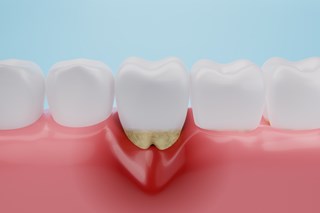

Behandlingar

Nedan finns en lista med behandlingar som vi utför. Klicka på knapparna för att läsa mer om just den behandlingstypen🦷